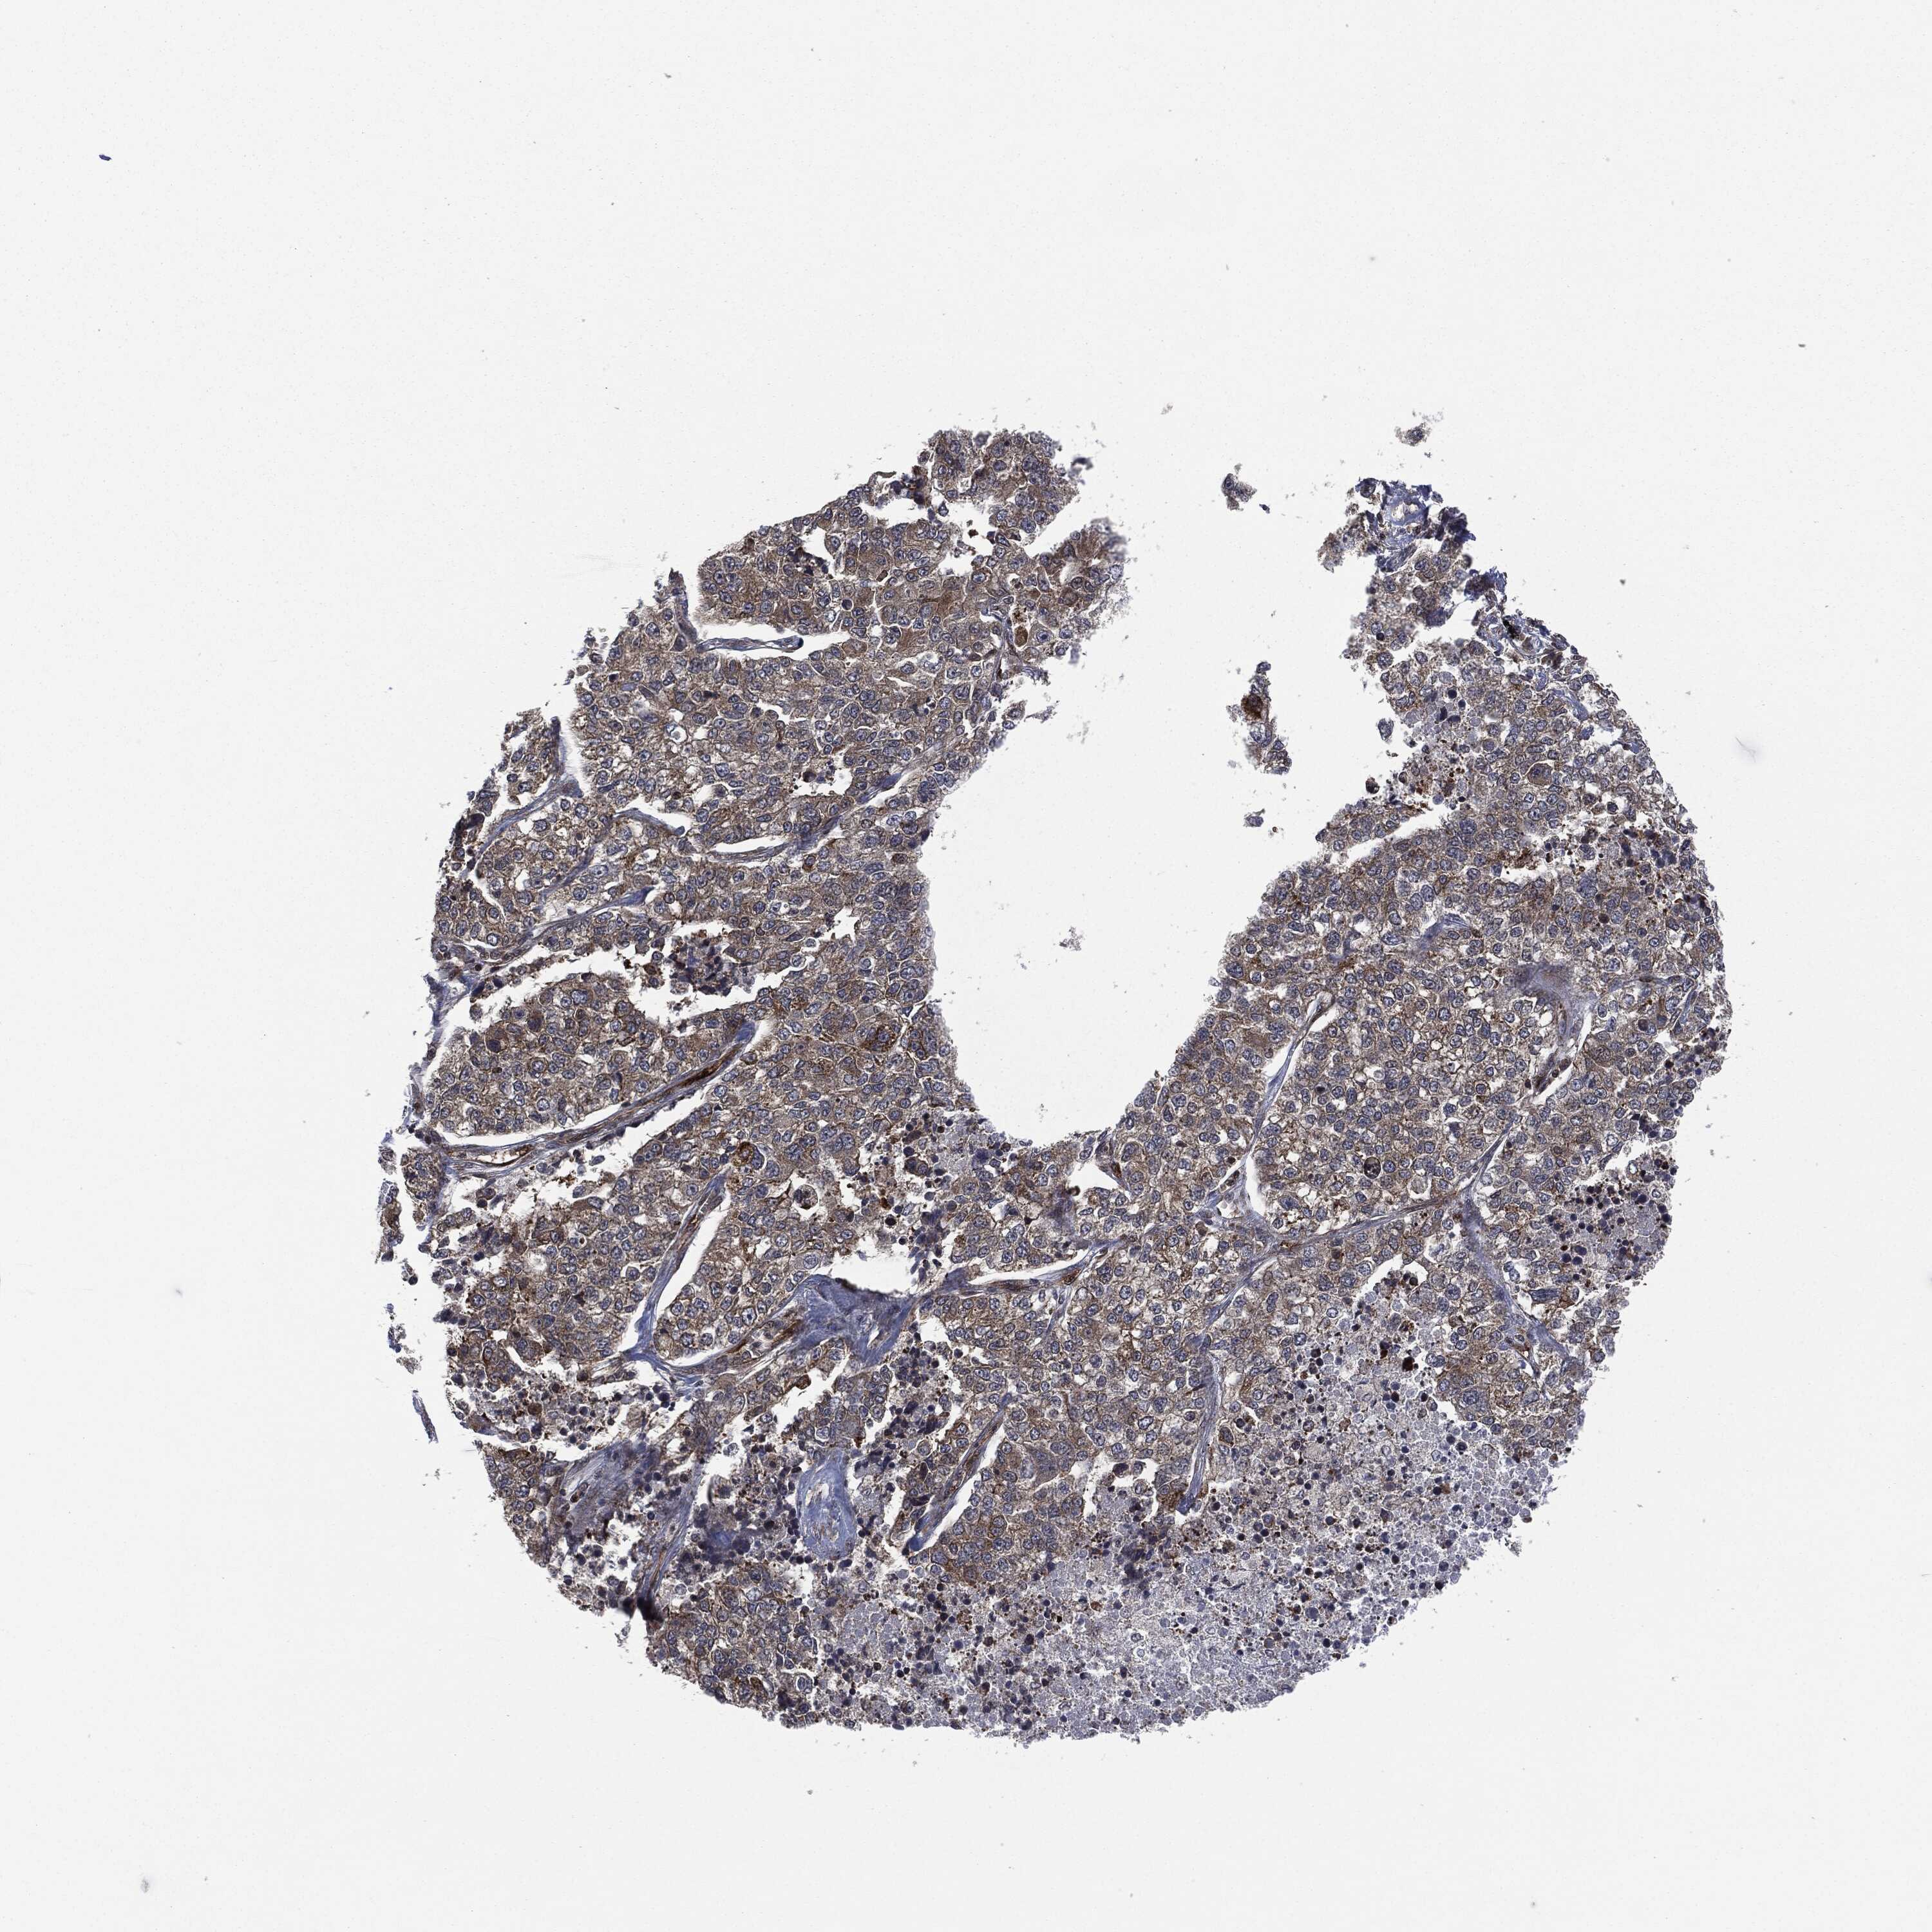

LUNG ADENOCARCINOMA (VALIDATION) - Interactive survival scatter ploti

The Survival Scatter plot shows the clinical status (i.e. dead or alive) for all individuals in the patient cohort, based on the same data that underlies the corresponding Kaplan-Meier plots. Patients that are alive at last time for follow-up are shown in blue and patients who have died during the study are shown in red.

The x-axis shows the expression levels (FPKM) of the investigated gene in the tumor tissue at the time of diagnosis. The y-axis shows the follow-up time after diagnosis (years). Both axes are complimented with kernel density curves demonstrating the data density over the axes. The top density plot shows the expression levels (FPKM) distribution among dead (red) and alive patients (blue). The right density plot shows the data density of the survived years of dead patients with high and low expression levels respectively, stratified using the cutoff indicated by the vertical dashed line through the Survival Scatter plot. This cutoff is automatically defined based on the FPKM cutoff that minimizes the p-score. The cutoff can be changed by dragging the vertical line or by entering a cutoff value in the square labeled "Current cut-off".

Under the Survival Scatter plot the p-score landscape (black curve; left axis) is shown together with dead median separation (red curve; right axis). Dead median separation is the difference in median mRNA expression between patients who have died with high and low expression, respectively. It is calculated as follows: median FPKM expression of dead patients with high expression - median FPKM expression of dead patients with low expression. This is intended to aid the user in visually exploring custom cutoffs and the associated p-scores and dead median separation.

Individual patient data is displayed and can be filtered by clicking on one or more of the category buttons on the top of the page. Categories describing expression level and patient information include: high, low, alive, dead, female, male and tumor stages. The scale of the x-axis can be toggled between linear and log-scale by clicking on the "x log" button. Mouse-over function shows TCGA ID, patient information and mRNA expression (FPKM) for each patient.

& Survival analysisi

Kaplan-Meier plots summarize results from analysis of correlation between mRNA expression level and patient survival. Patients were divided based on level of expression into one of the two groups "low" (under cut off) or "high" (over cut off). X-axis shows time for survival (years) and y-axis shows the probability of survival, where 1.0 corresponds to 100 percent.

HRAS is not prognostic in Lung Adenocarcinoma (validation)

: 12.22

P scorei

N/A

Average pTPM 8.6

Number of samples 105